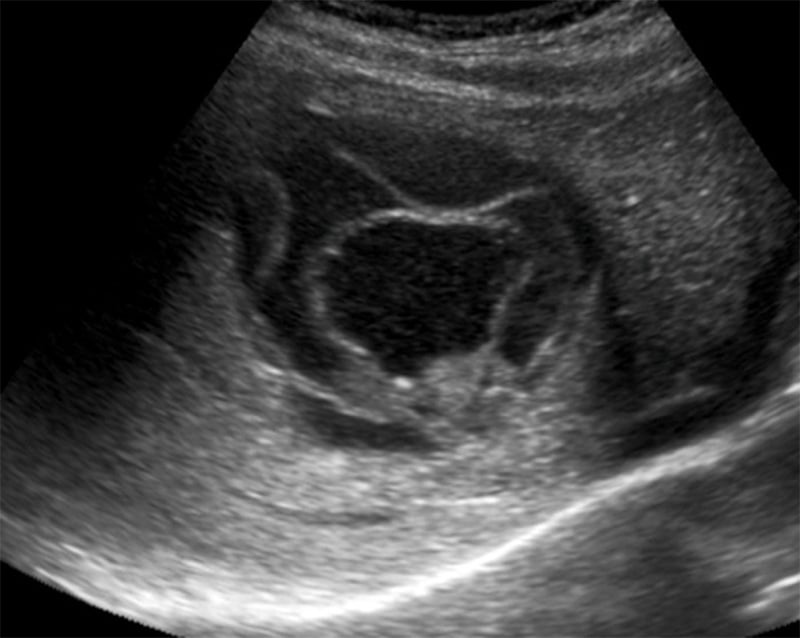

- CE2: Multiple discrete daughter cysts inside the original cystic capsule, forming a honeycomb pattern.

Figure 42. Large single CE2 hydatid cyst with several daughter cysts inside giving characteristic honeycomb appearance. Note the lack of color flow and calipers marking the outer margins in (B). (Case courtesy of Dr Pir Abdul Ahad Aziz Qureshi, radiopaedia.org. From the case rID: 68473, accessed 4/14/21)